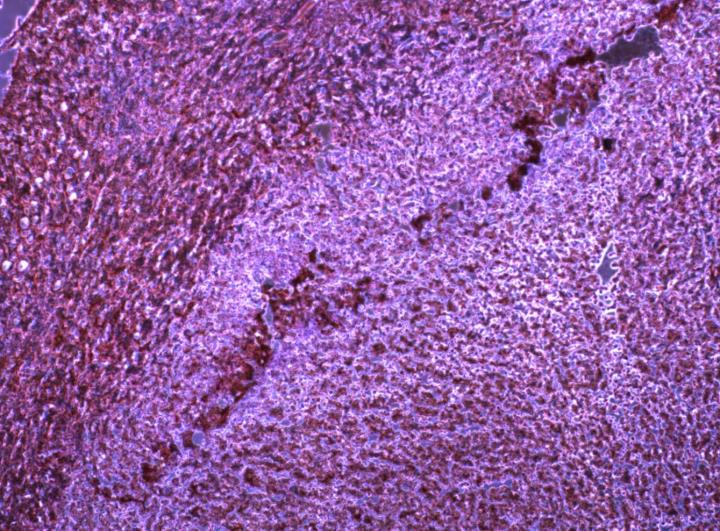

LA JOLLA--(September 18, 2017) The immune system automatically destroys dysfunctional cells such as cancer cells, but cancerous tumors often survive nonetheless. A new study by Salk scientists shows one method by which fast-growing tumors evade anti-tumor immunity.

Cancerous tumors often grow so fast that they use up their available blood supply, creating a low-oxygen environment called hypoxia. Cells normally start to self-destruct under hypoxia, but in some tumors, the microenvironment surrounding hypoxic tumor tissue has been found to help shield the tumor.

MicroRNAs--small, noncoding RNA molecules that regulate genes by silencing RNA--have increasingly been implicated in tumor survival and progression. To better understand the connection between microRNAs and tumor survival, the researchers screened different tumor types for altered levels of microRNAs. They identified two microRNAs--miR25 and miR93-- whose levels increased in hypoxic tumors.

That is exactly what the team confirmed with further experiments. Using mouse models and tissue samples, the researchers found that a low-oxygen (hypoxia) state triggered miR25 and miR93 to set off a chain of cell signaling that ultimately lowered cGAS levels. If the researchers inhibited miR25 and miR93 in tumor cells, then cGAS levels remained high in low-oxygen (hypoxic) tumors.

Researchers could slow tumor growth in mice if they inhibited miR25 and miR93. Yet, in immune-deficient mice, the effect of inhibiting miR25 and miR93 was diminished, further indicating that miR25 and miR93 help promote tumor growth by influencing the immune system.